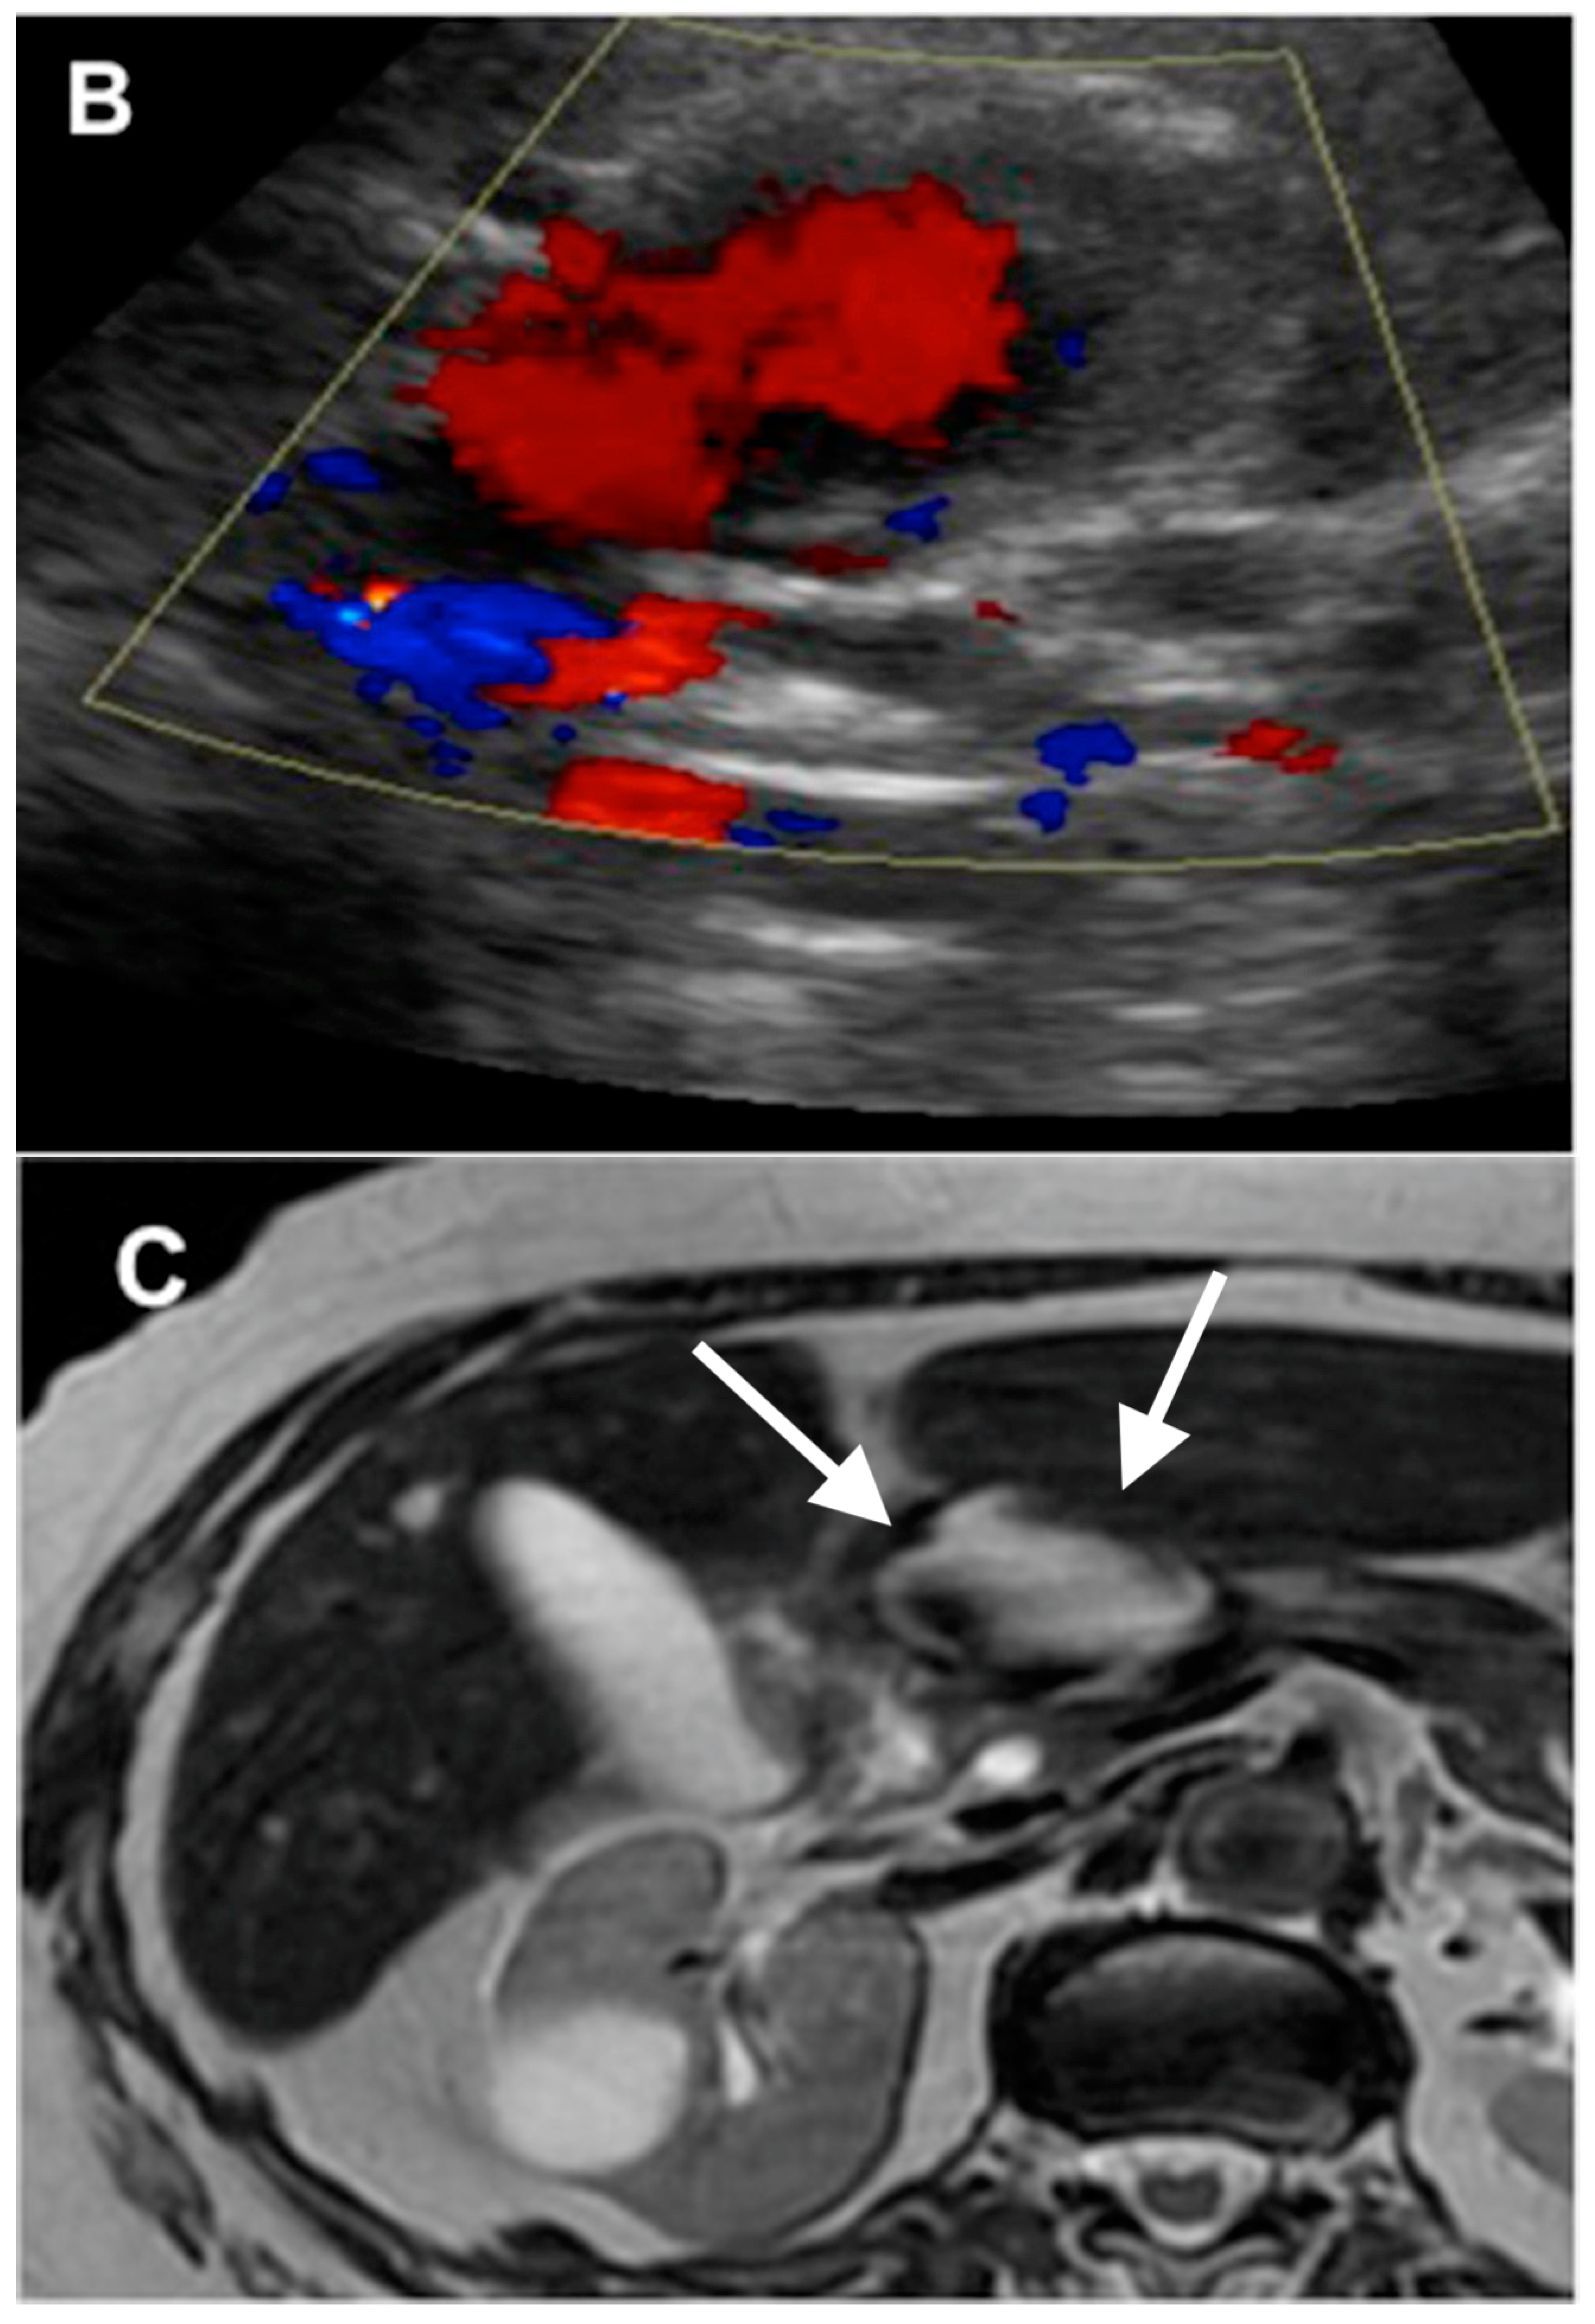

4. GDA Pseudoaneurysm Embolization

- Volpi, M.A.; Voliovici, E.; Pinato, F.; Sciuto, F.; Figoli, L.; Diamant, M.; Perrone, L.R. Pseudoaneurysm of the gastroduodenal artery secondary to chronic pancreatitis. Ann.Vasc. Surg. 2010, 24, 1136.e7–1136.e11. [Google Scholar] [CrossRef] [PubMed]

- Naitoh, I.; Ando, T.; Shimohira, M.; Nakazawa, T.; Hayashi, K.; Okumura, F.; Miyabe, K.; Yoshida, M.; Togawa, H.; Sasaki, S.; et al. Hemosuccus pancreaticus associated with segmental arterial mediolysis successfully treated by transarterial embolization. JOP 2010, 110, 625–629. [Google Scholar]

- Bloechle, C.; Izbicki, J.; Rashed, M.; El-Sefi, T.; Hosch, S.; Knoefel, W.; Rogiers, X.; Broelsch, C.E. Hemobilia: Presentation, diagnosis, and management. Am. J. Gastroenterol. 1994, 89, 1537–1540. [Google Scholar] [PubMed]

- Srivastava, D.N.; Sharma, S.; Pal, S.; Thulkar, S.; Seith, A.; Bandhu, S.; Pande, G.K.; Sahni, P. Transcatheter arterial embolization in the management of hemobilia. Abdom. Imaging 2006, 31, 439–448. [Google Scholar] [CrossRef] [PubMed]